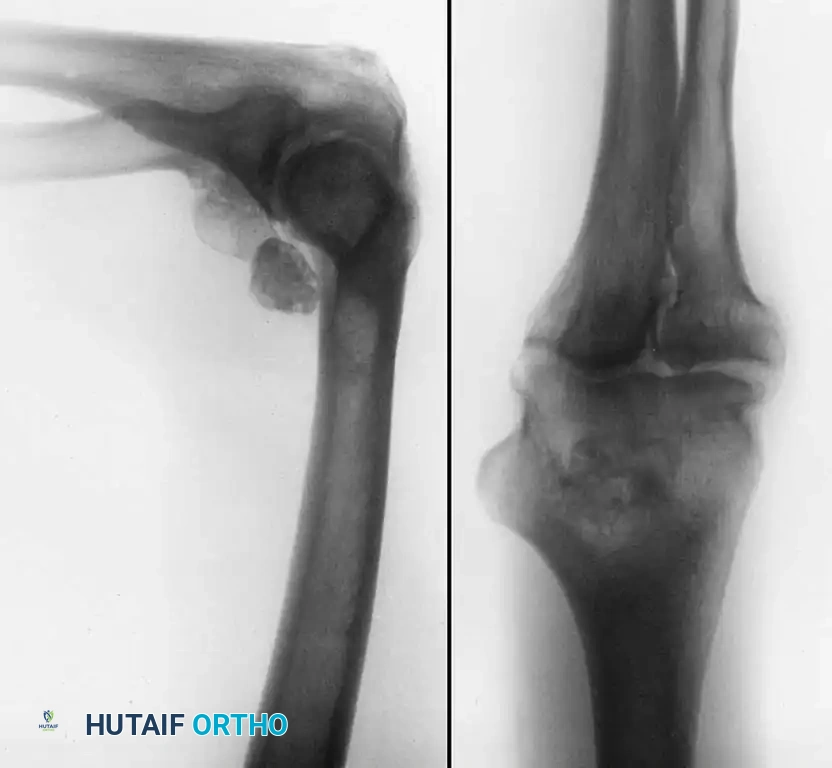

- Loose Body Removal: Evaluation and extraction of chondral or osteochondral loose bodies, which frequently reside in the olecranon or coronoid fossae.

- Degenerative Joint Disease: Excision of impinging osteophytes from the humerus (coronoid/olecranon fossae) and the olecranon tip to restore terminal extension and flexion.

- Inflammatory Arthropathy: Partial or subtotal synovectomy, which is particularly beneficial in patients with rheumatoid arthritis or synovial chondromatosis.

- Arthrofibrosis: Débridement and lysis of intra-articular adhesions in posttraumatic or severe degenerative disease to restore range of motion.

- Diagnostic Dilemmas: Evaluation of the chronically painful elbow when advanced imaging (MRI, CT arthrography) and other diagnostic tests remain inconclusive.

Furthermore, the arthroscope is increasingly utilized for the débridement of inflamed olecranon bursae, arthroscopic-assisted stabilization procedures (e.g., LUCL plication), and the reduction and internal fixation of select intra-articular fractures (such as radial head or capitellar shear fractures).